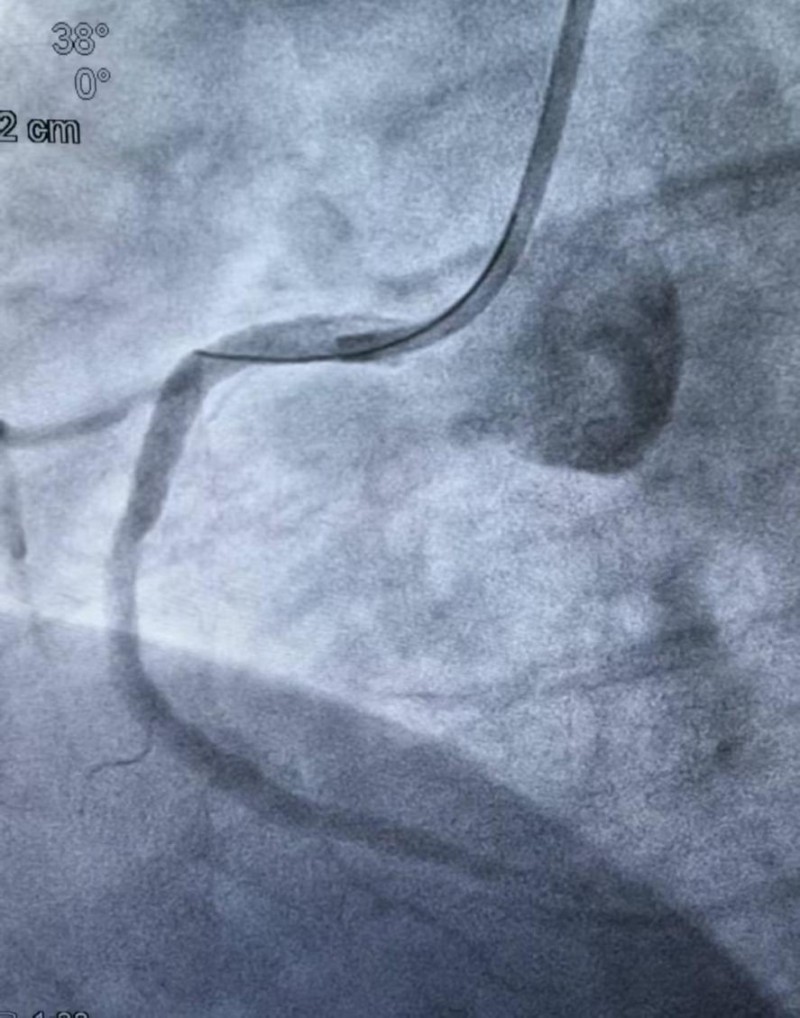

造影结果明确后,介入团队沉着应对,制定个体化方案,依次实施球囊扩张、血栓抽吸、冠脉内溶栓,精准清除血栓,解除血管闭塞,成功植入3枚支架,完全恢复冠脉血流,术后患者胸痛症状即刻缓解。

(术后)术后患者出现反复心衰发作,心血管内科团队立即启动

强化抗心衰治疗,给予精准药物调控、严密监护、精细化护理与个体化康复管理,逐一纠正心功能不全,稳定生命体征。经过9天精心救治,患者生命体征平稳、心功能逐步恢复,胸痛未再发作,于2月4日顺利康复出院。 初心与使命:守护健康,我们一直在路上